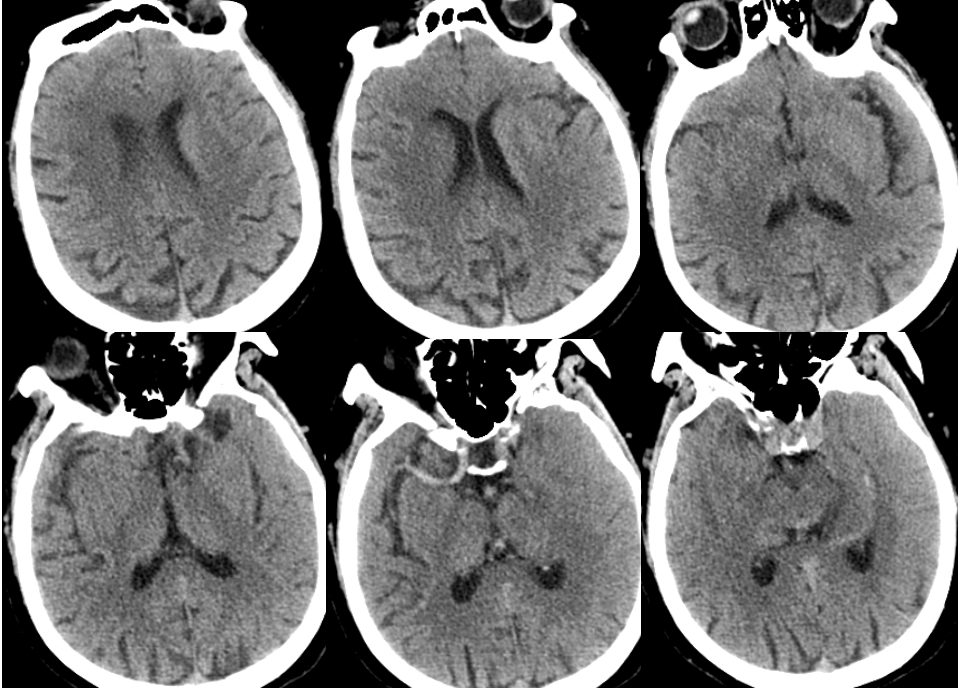

梗死合并少量出血,暂不给与抗凝抗血小板药物,给与脱水、营养神经、清除脑自由基、改善循环、补液营养支持以及抗感染等药物治疗。

术后5月复查CTA显示右侧颈内动脉及大脑中血流通畅。